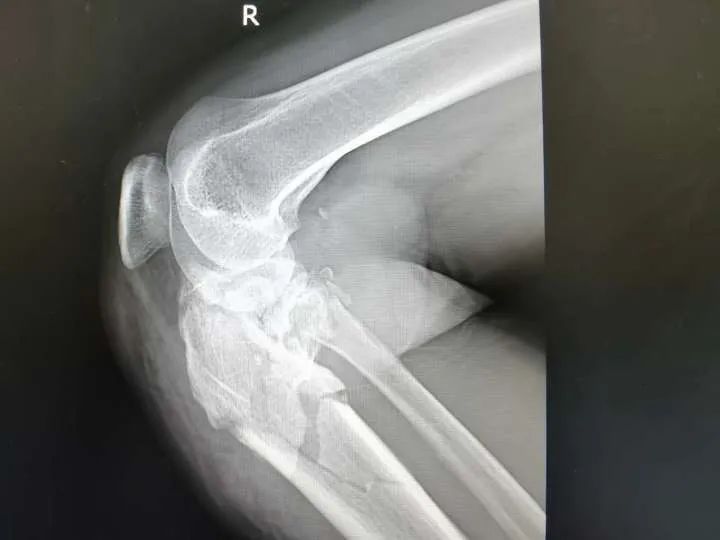

近期, 家住西乡县杨河镇的马女士骑着单车不慎重重摔倒,当即出现右膝关节肿胀、疼痛,腿无法再动弹,随后被送到西乡县中医医院。经急诊科检查诊断为“右胫骨近端粉碎性骨折合并膝关节脱位”,随即马女士入住骨三科。当班医生刘勇接诊后发现患者右膝部肿胀明显,疼痛拒按,关节极度屈曲,不能伸直,外形畸形,触摸足背动脉较健侧明显减弱。结合X线片检查,刘医生告知患者及家属,可以先复位固定纠正膝关节脱位,解除断骨对神经及血管的压迫。手法复位是西乡县中医院骨伤科传统技艺,多年来代代相授、传承改进,已形成中医院骨伤科独特的优势技术。马女士受伤后第一时间来到中医院,也算是慕名而来。随后刘勇医生和董兵医生密切配合,为患者先行脱位手法复位并石膏外固定制动,复位后马女士立即感觉右膝疼痛明显缓解!

为了尽量缩短马女士康复时间,科主任孙明军组织科内会诊,经过反复分析和调整,为患者制定了详细、周密、个性化的治疗方案。先以局部针刺减压,并抗炎、消肿止痛、补液、对症治疗症状缓解后,再采取胫骨近端内外侧锁定板固定手术(右胫骨近端粉碎性骨折切腹内固定术+同种异体骨植骨术+膝关节腔清理术)。

粉碎性骨折是一种骨折类型,其特点是骨折端的骨组织在受伤时被压碎成多个碎片。这种骨折常见于高速交通事故、高坠落、重型碾压等严重外力作用下。由于骨折端的骨组织碎片较多且不稳定,这类骨折常伴随有明显的疼痛、肿胀、变形和活动受限等严重症状。粉碎性骨折需要经过专业的治疗和严密的监护,通常会进行手术切复内固定或异体植骨等复杂手术,以稳固骨折端并促进骨折的愈合。

膝关节脱位是指膝关节内髁和外髁的关节面完全脱离,使得膝关节处于不正常的位置。这种情况通常由剧烈的外力作用引起,例如运动损伤、车祸或跌倒等。膝关节脱位严重影响患者的行走和活动能力,会出现严重的关节疼痛、肿胀、变形和不能正常活动等症状。治疗膝关节脱位需要及时复位,并进行综合治疗,如康复锻炼和康复理疗,以恢复关节功能。